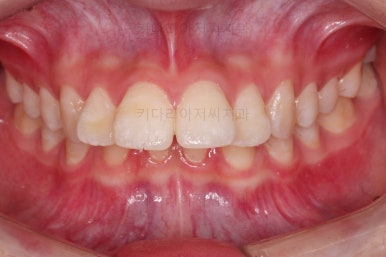

교합이 잘 맞아졌고요.

위아래 앞니도 서로 가까워졌어요.

치열도 가지런해졌고, 과개교합도 잘 개선이 되었습니다.

연산동치아교정 이제 전후 사진을 비교해 볼게요.

아래 앞니가 2개인 것이 표시가 안날 정도로 자연스럽게 교합이 맞아졌습니다.